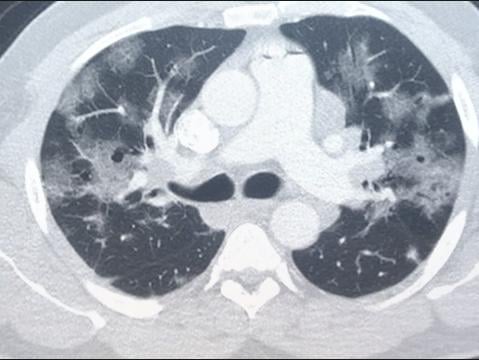

20210112 The researchers also identified immune cells -- macrophages and T cells -- that could be important targets when treating severe COVID-19. Control your fever with aspirin nonsteroidal anti-inflammatory drugs NSAIDs such as ibuprofen or naproxen or acetaminophen. 20200323 In people who get COVID-19 pneumonia that haze tends to cluster on the outside edge of both lungs by the ribs a distinctive pattern said Dr.

Ct Imaging And Clinical Course Of Asymptomatic Cases With Covid 19 Pneumonia At Admission In Wuhan China Journal Of Infection

Covid 19 Radiology Reference Article Radiopaedia Org

Temporal Lung Changes On Thin Section Ct In Patients With Covid 19 Pneumonia Scientific Reports